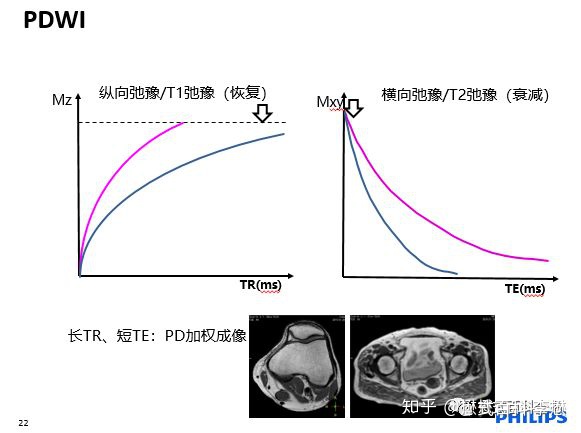

在传统的磁共振SE自旋回波序列中,我们主要是调整两个参数TE(回波时间)和TR(重复时间)来改变磁共振图像所主要反映的组织特性。

搞磁共振的人都知道一个口诀:

长TR,长TE,是T2加权像;

短TR,短TE,是T1加权像;

长TR,短TE,是PD加权像。

我们不用死记硬背,直接用三个图像来记忆。

TR越长,组织的纵向弛豫恢复越彻底,那么组织之间的纵向弛豫差异(T1)的差异被削弱;TE越长,代表回波时间越长,组织在横向之间的弛豫差异会被拉大,组织的T2差异会越大。(我们可以做一个思维实验,极端情况下,想象TE为0,那么组织之间在横向上的弛豫差异根据就来不及显示,因为TE=0ms,组织之间就没有T2差异了,所以TE越长,理论上组织之间的T2差异越大)。当然,TE也不能无限长,太长以后,所有组织信号全部衰减完了,等于又没有T2差异了。

TR越长,组织的纵向弛豫恢复越彻底,那么组织之间的纵向弛豫差异(T1)的差异被削弱,所以要得到T1差异,TR不能长;TE越长,代表回波时间越长,组织在横向之间的弛豫差异会被拉大,组织的T2差异会越大。所以,要削弱T2差异,就要让TE短。所以,为什么短TR,短TE,突出的是组织的T1对比。

好了,我们现在要得到反映质子密度的权重图像,就是要尽量削弱T1和T2对图像的影响。那么也很简单,长TR,削弱组织之间的T1对比;短TE,削弱组织之间的T2对比。